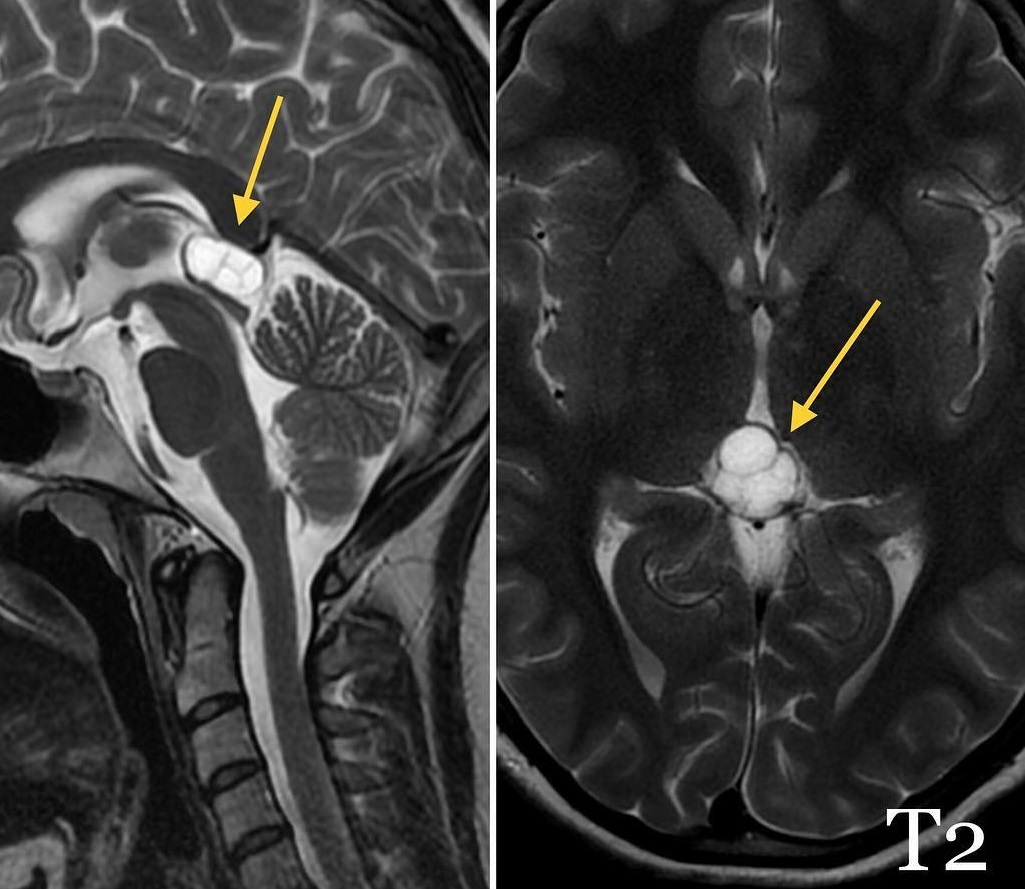

Симптомы кисты эпифиза